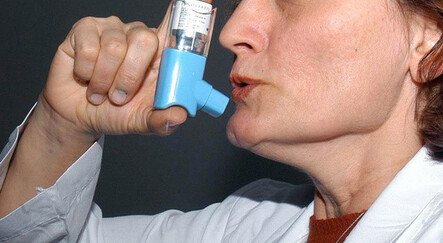

Günümüzde pek çok kişide görülen astım, halk sağlığı sorunu olarak sıklıkla karşımıza çıkıyor. Hırıltı, nefes darlığı, göğüste sıkışma ve öksürük gibi solunum sistemi şikayetleri ile kendini belli ediyor. Başta sigara olmak üzere birçok faktör ise astımı tetikliyor. Bu etkenlerden bahseden Göğüs Hastalıkları Uzmanı Doç. Dr. Nilüfer Aykaç, konuyla ilgili önemli uyarılar ve önerilerde bulundu.

Yaz aylarında bazı kurallara uyulmadığında tetiklenebilen astım, hava yollarının daralması ile kendini gösteren ve ataklar halinde gelen bir hastalık. Son yıllarda yaygınlaşarak ülkemizde yaklaşık her 100 erişkinden 9’unda, her 100 çocuktan 15’inde görülür hale geldi. Peki, astımı tetikleyen etkenler neler? İşte konuyla ilgili önemli bilgiler…